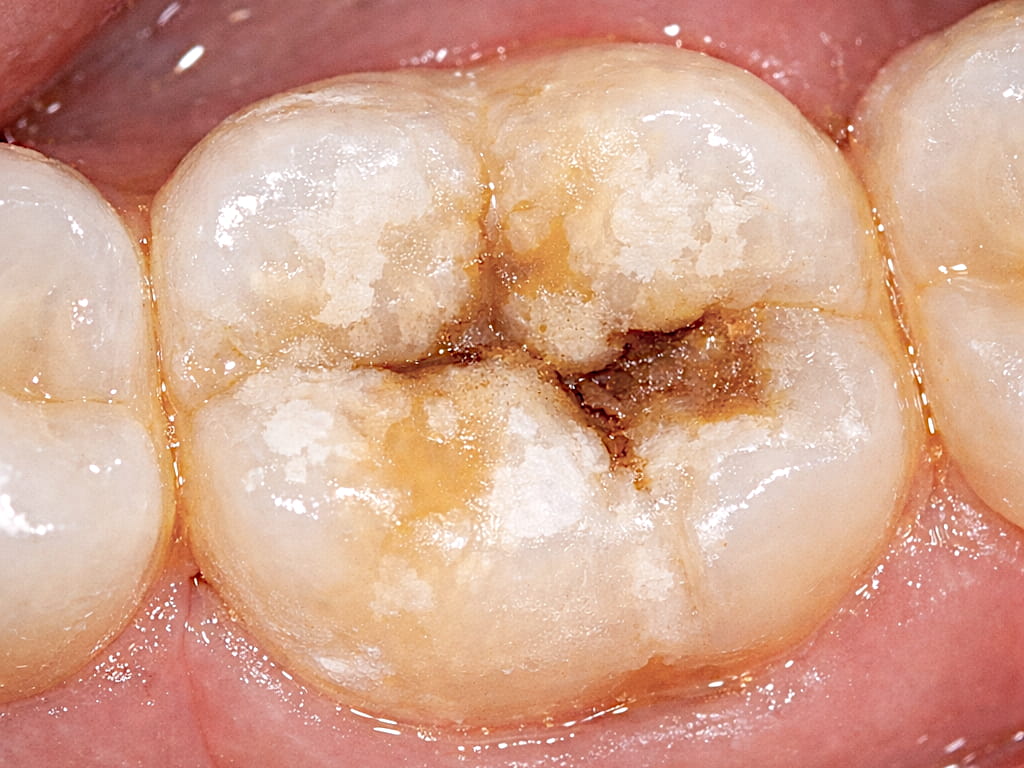

Typisch sind auffällige Flecken auf der Zahnoberfläche. Diese können ganz unterschiedlich aussehen. Manche Stellen sind kreidig weiß, andere eher gelblich oder bräunlich. Oft wirken die betroffenen Bereiche weniger glänzend als gesunder Zahnschmelz.

Gelbliche oder bräunliche Bereiche sind dabei häufig ein Hinweis darauf, dass der Zahnschmelz an dieser Stelle besonders geschwächt ist.

Bei manchen Kindern wirkt der Zahnschmelz außerdem porös oder brüchig. In stärker ausgeprägten Fällen können kleine Stücke des Zahnschmelzes abbrechen, besonders an den Backenzähnen.